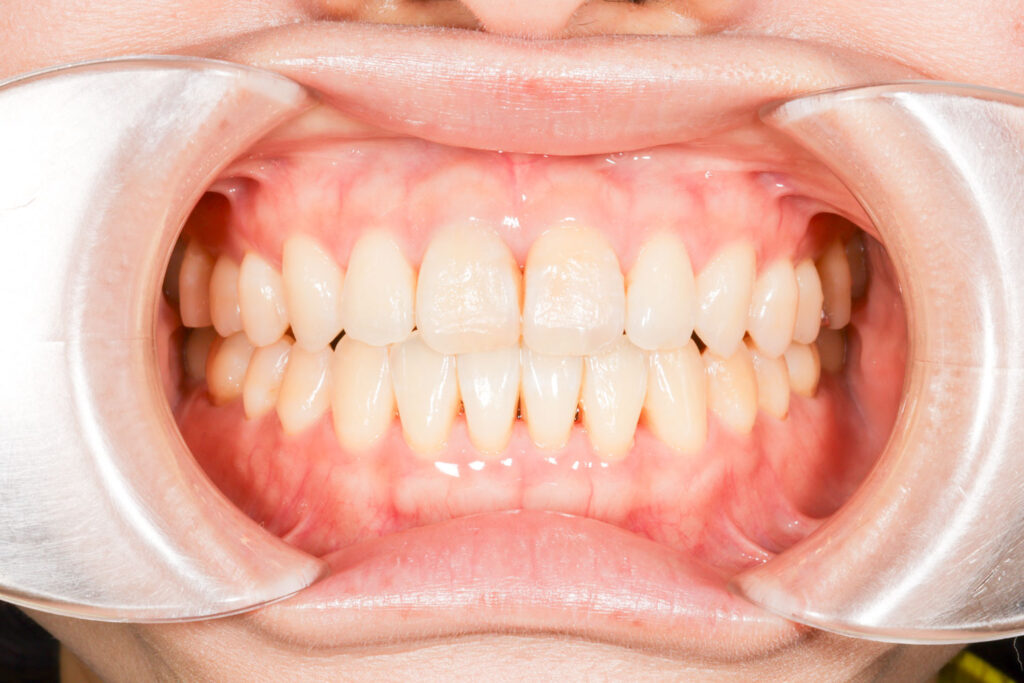

Before

After

年齢 10代

治療装置 上は裏側の矯正装置(ハーフリンガル)

治療内容 上下左右4本抜歯

治療期間 2年8か月

リスク 歯の移動に伴う痛み、歯肉退縮、歯根吸収、歯肉炎、虫歯

主訴 八重歯が気になる

症状 叢生(ガタガタ)

治療回数 33回程度

総額費用 125万円程度